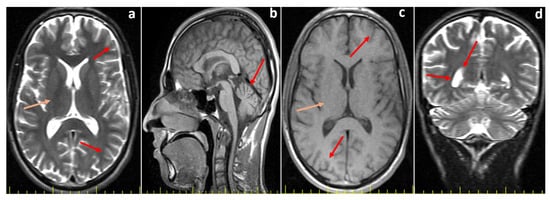

Biallelic Truncating DNAH14 Variant in Siblings with Neurodevelopmental Disorder and Predominant Ataxia: Clinical Report and Literature Review

by Savas Baris, Mustafa Dogan, Kerem Terali, Alper Gezdirici, Recep Eroz, Peren Perk Yucel, Huseyin Kilic, Cuneyd Yavas, Gizem Yildirim and Ibrahim Baris

Int. J. Mol. Sci. 2026, 27(2), 575; https://doi.org/10.3390/ijms27020575 - 6 Jan 2026

Neurodevelopmental disorders (NDDs) with ataxia are genetically heterogeneous and remain a diagnostic challenge. Recent advances in genomic technologies have facilitated the identification of rare, potentially causative variants in genes not traditionally associated with classic NDD phenotypes. The DNAH14 gene, encoding a dynein axonemal heavy chain involved in ciliary motility, has recently emerged as a novel candidate in neurological syndromes. Here, we report two Turkish siblings presenting with late-onset balance disorder, progressive ataxia, and cognitive impairment. Initial genetic analysis revealed that both siblings also harbor FXN GAA repeat expansions consistent with pathogenic Friedreich’s ataxia (FRDA). To elucidate the molecular basis of the patients’ cognitive impairment, whole-exome sequencing was performed. This analysis identified a novel homozygous frameshift variant in the DNAH14 gene, located within the conserved linker domain upstream of the motor core, which is critical for ATP hydrolysis and microtubule interactions. The variant is absent from population databases, predicted to be deleterious by multiple in silico algorithms, and segregates in the family in a manner consistent with autosomal recessive inheritance. The coexistence of FRDA expansions and a truncating DNAH14 variant suggests a potential dual genetic contribution to the observed phenotype, in which FRDA-associated pathology likely underlies the ataxia, while DNAH14 disruption may contribute to additional neurodevelopmental features. This is the first report describing the co-occurrence of FRDA and a homozygous truncating DNAH14 variant in the same individuals, broadening our understanding of overlapping neurogenetic mechanisms. Our findings expand the phenotypic spectrum of DNAH14-related disorders and highlight the importance of considering multilocus pathogenic variants in patients with complex or atypical ataxia presentations. Full article

Figure 1